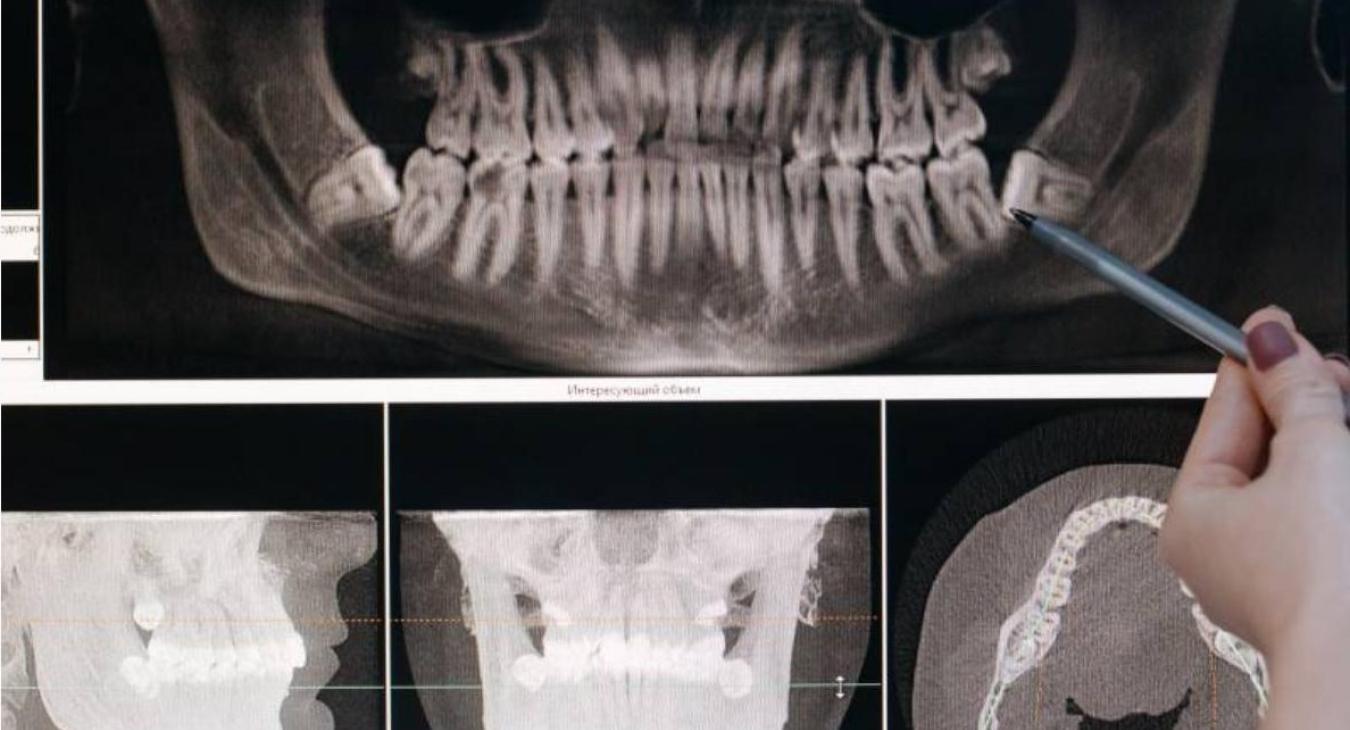

Tomografia computerizzata (Cone Beam Computed Tomography CBCT)

La tomografia computerizzata è un tipo di imaging intraorale essenziale per il dentista digitale. Si tratta di uno strumento di diagnosi radiologica tridimensionale utile all’acquisizione di immagini necessarie per la progettazione di interventi di chirurgia implantare.

Essa fornisce informazioni sull’anatomia ossea, in formato 3D, del paziente. I dati raccolti vengono poi utilizzati per la progettazione di impianti ossei e impianti custom made (personalizzati).